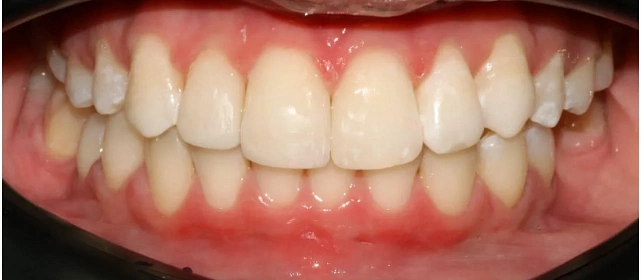

Проблема: В клинику обратилась пациентка — беспокоили неровные зубы и неправильное смыкание. Зубные ряды сходились некорректно, зубы стояли со смещением, что влияло и на внешний вид, и на распределение нагрузки при жевании.

Решение: Поставили элайнеры 3D Smile на обе челюсти. Лечение заняло 4 года и потребовало нескольких последовательных этапов коррекции. Капы менялись каждые 1–2 недели, на контрольных визитах отслеживали прогресс и выдавали новые наборы. Зубы встали в правильное положение, смыкание нормализовалось. Зафиксировали ретейнеры на обе челюсти, изготовили ретенционные капы. Пациентка прошла онлайн-консультацию с ортопедом для оценки дальнейших шагов.

Лечение потребовало нескольких последовательных этапов — каждый дозаказ кап уточнял положение зубов, которые не полностью отреагировали на предыдущий курс. Элайнеры 3D Smile позволяют работать поэтапно, корректируя план по ходу. Результат получен, ретейнеры зафиксированы. Рекомендовала пациентке консультацию ортопеда для оценки состояния зубов после лечения